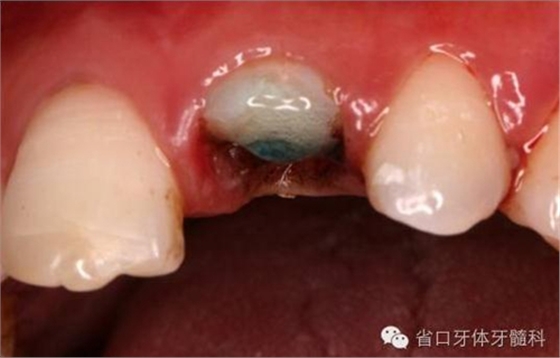

圖2. 術前口內(nèi)照片,21/冠折。

圖4. 拔除斷冠后的唇面照片